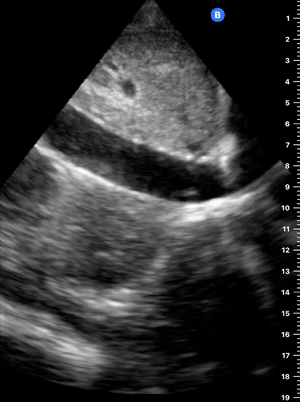

This view looks at the heart from the apex. When done properly, it achieves a horizontal cut of the heart that demonstrate all four chambers simultaneously. Consequently, its main utility is to assess the relationship between LV and RV. Beware, differentiating the chambers by ventricle size or thickness is not recommended, and it could lead to confusion in case of RV enlargement.

ORIENTATION & TECHNIQUE

Place the transducer at the apex beat and angle it towards the right scapula. The correct image results from sliding the probe until the interventricular septum is in the middle of the screen, vertically dividing both sides of the heart. If using a cardiac preset, the probe’s marker points towards the patient’s left arm. Simpler, in this view, the probe notch should meet the marking on the screen, which is fundamental to avoid confusion.